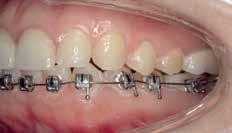

10 Dental News Quarter II Mini screw Assisted Limited Orthodontic Tooth Movement: About 2 Cases Reports

Case 1

Non extraction treatment, with mesial root movement and protraction of the mandibular second and third molars in order to close the residual space, create a solid contact between the mandibular second molar and second premolar without the need for prosthetic dental implant or crown. This option would require longer orthodontic treatment time with extensive follow up visits, however no extra cost is allocated for surgical and prosthetic procedures. (Figures 1 and 2)

Bonding: Genius Passive self ligation ( MEM Corporation, Sweden Taiwan) with 14 NiTi (Thermal ultra) engaged. First molar bondable tube with a built in long extended hook that reached the level of the furcation to apply the force close to the center of resistance of the second mandibular molar.

Figure 1 Figure 2